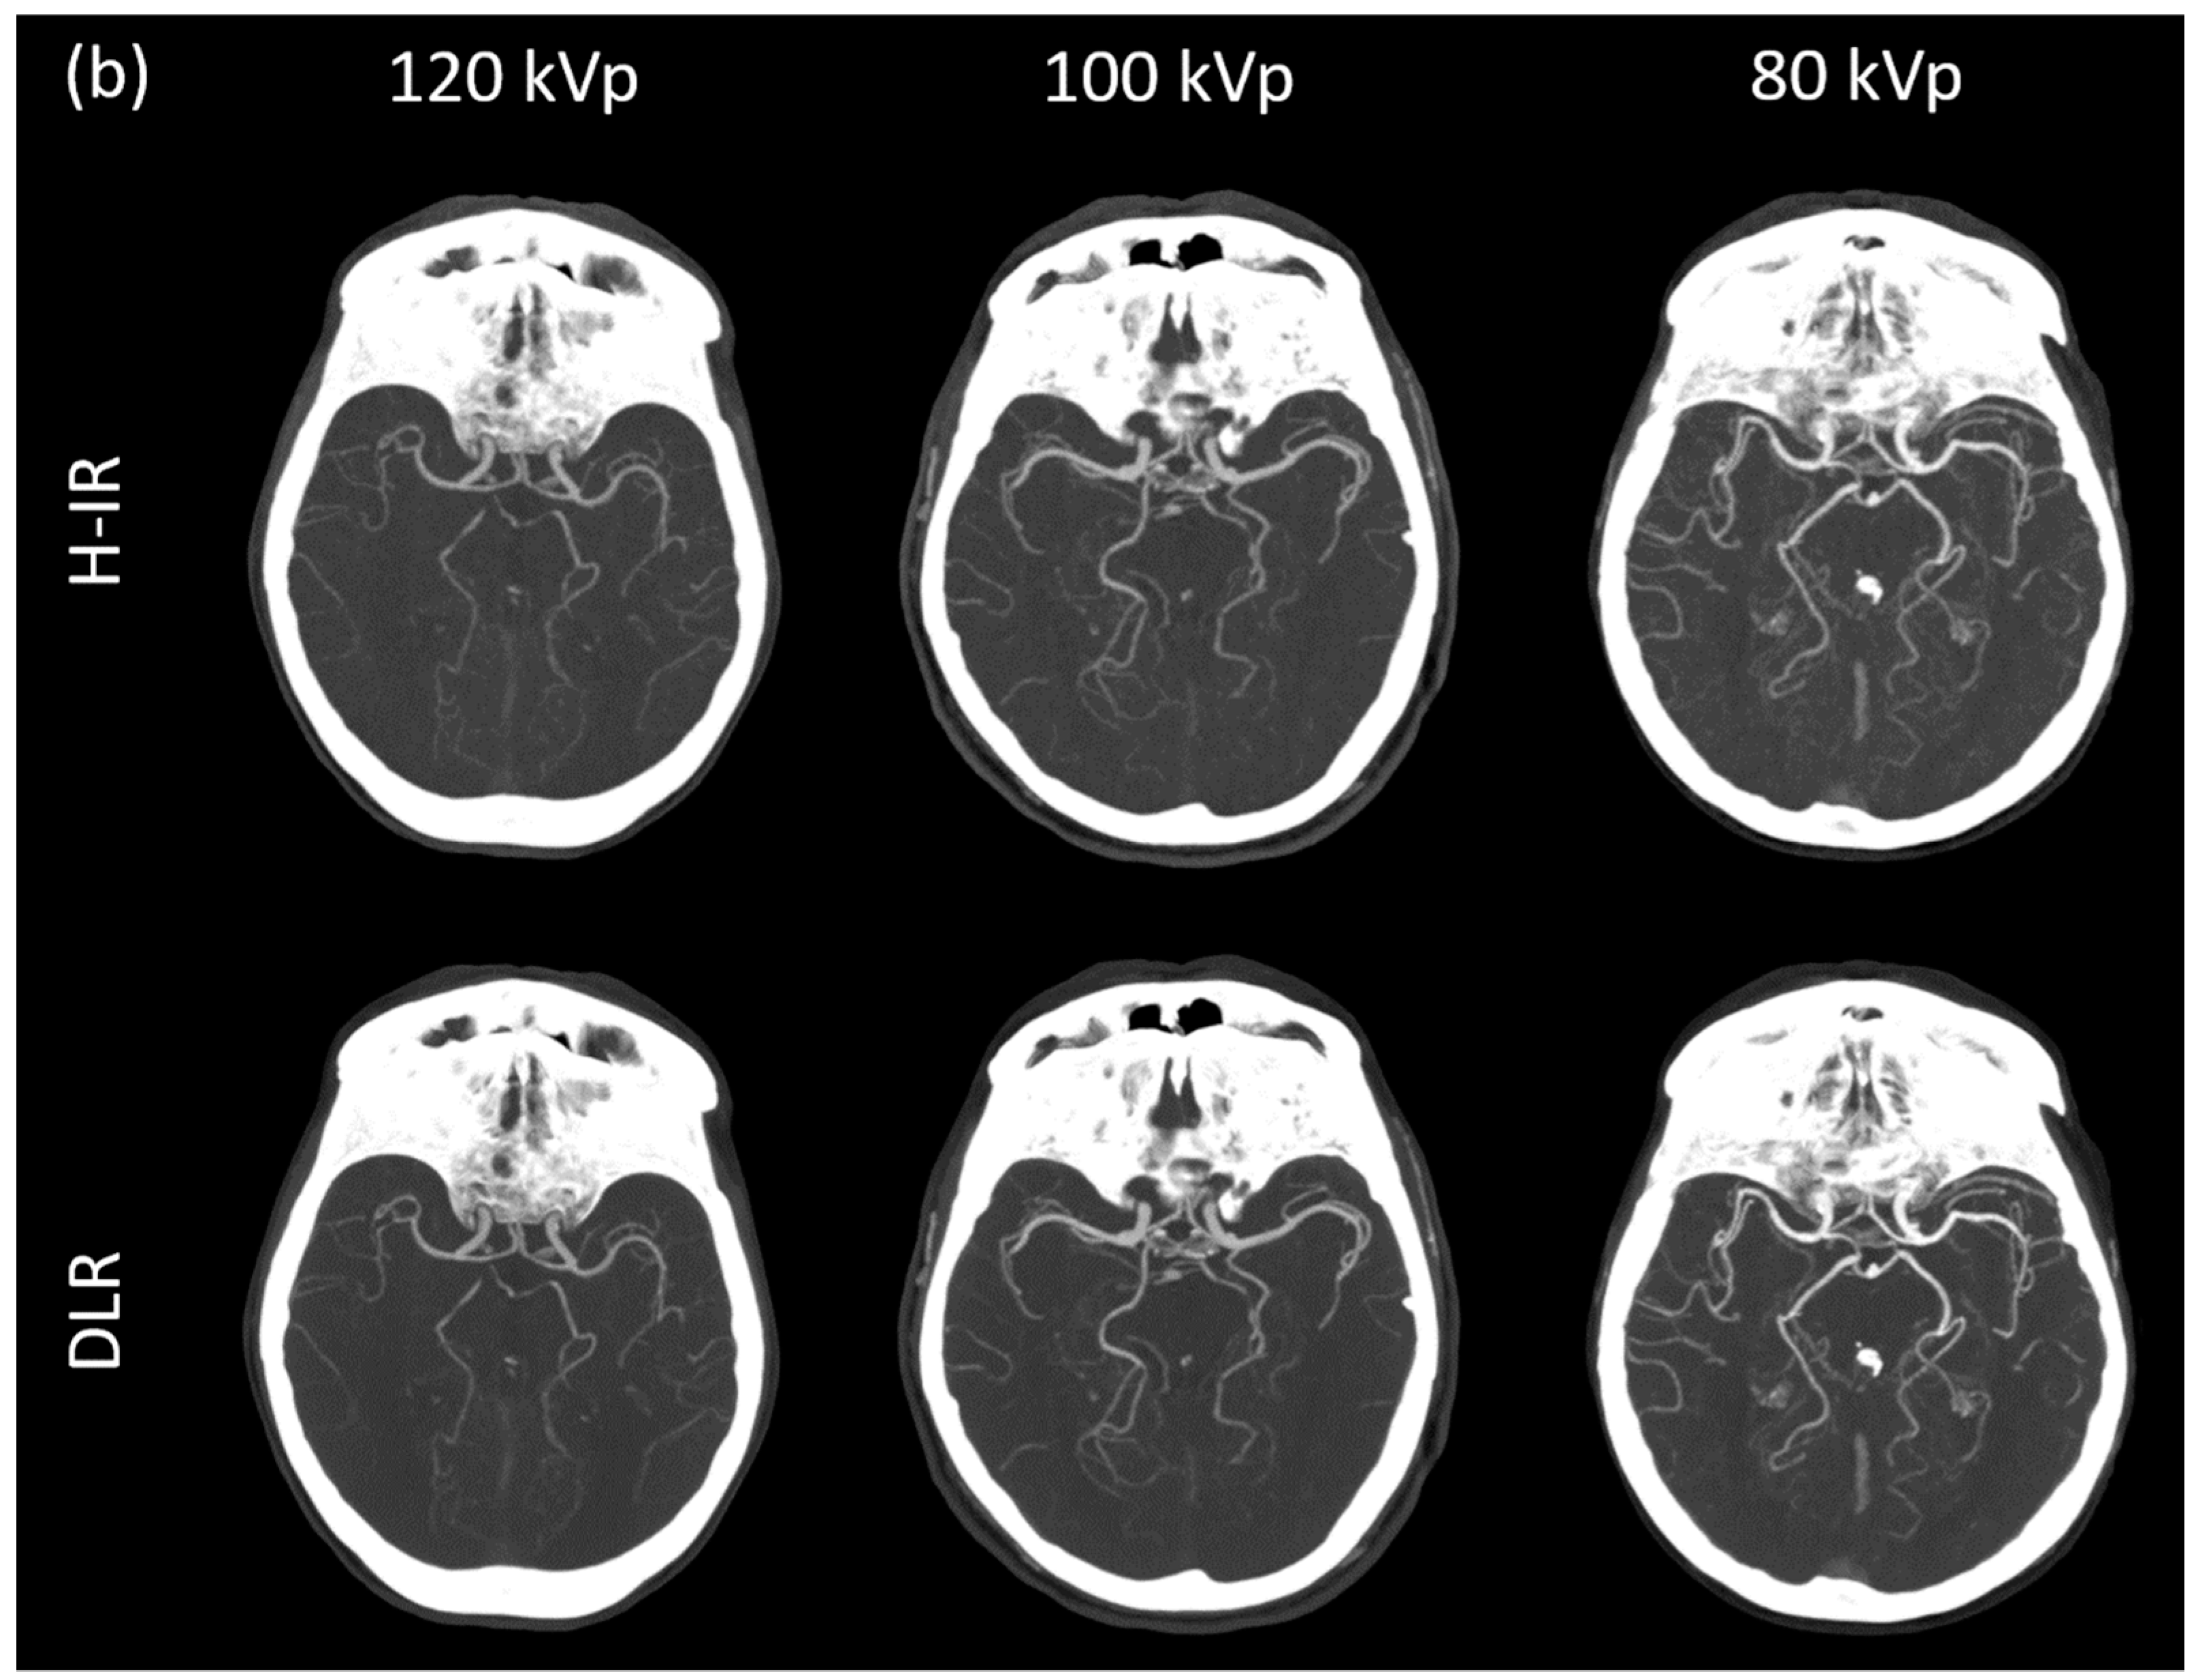

3.3.1. Image Signal Fluctuation with DLR vs. H-IR

3.3.2. Comparison of the Two Reconstruction Techniques at Constant kVp Value

3.3.3. Comparison of Low kVp plus DLR vs. Standard kVp plus DLR

3.3.4. Comparison of Low kVp plus DLR vs. Standard kVp plus H-IR

3.4. Qualitative Image Analysis